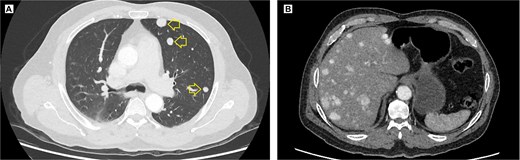

Contrast-enhanced thoracic and abdominal CT scan. (A) Axial view in the lung window of the thorax, solid hyperenhancing parenchymal nodules (arrow) ranging from 5 to 12 mm are observed in the left lung. (B) Coronal view in the soft tissue window, solid hyperenhancing nodules measuring 10 to 28 mm with diffuse distribution are observed.